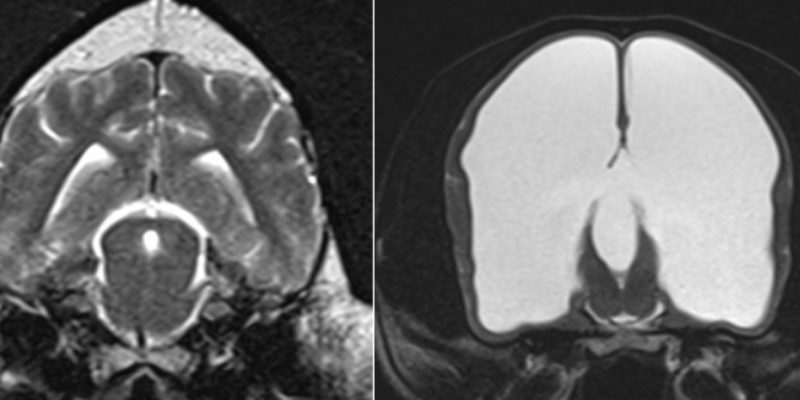

A brain MRI of a normal dog brain (left) and a hydrocephalic dog brain (right), Animal Emergency & Referral Center of Minnesota

Pictured is a brain MRI of a normal dog brain (left) and a hydrocephalic dog brain (right).